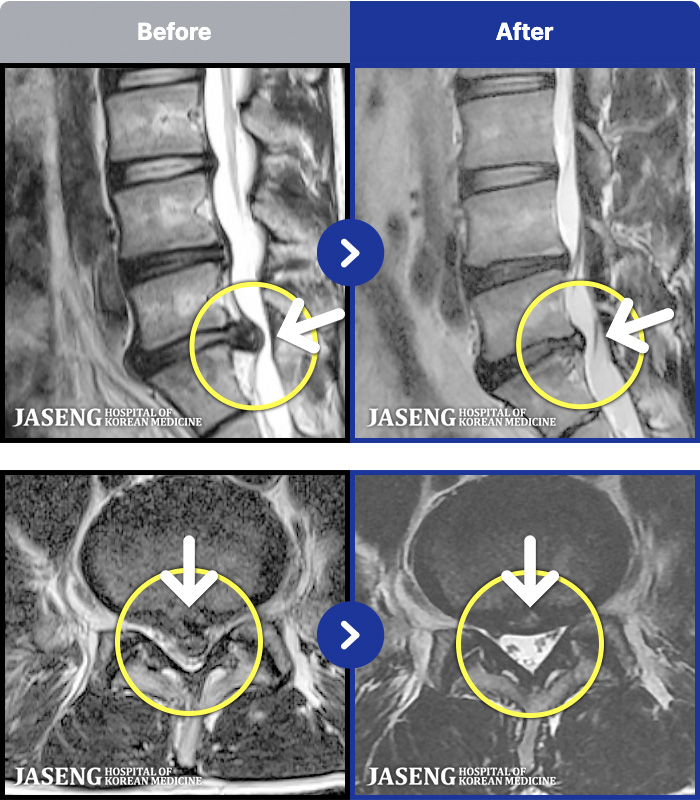

54 MRI ũ ʸ Ȯϼ.